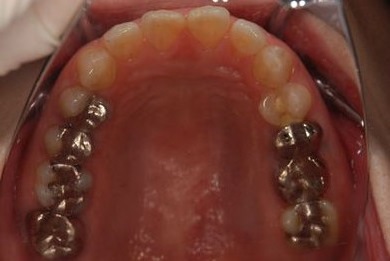

抜歯即日スピードインプラント治療+セラミック治療+歯肉歯槽骨整形術

| 治療内容 | インプラント2本(抜歯即日スピードインプラント)、ハイブリッドセラミッククラウン2本、歯肉歯槽骨整形術 | ||||||||||||||||||||||||||||||||